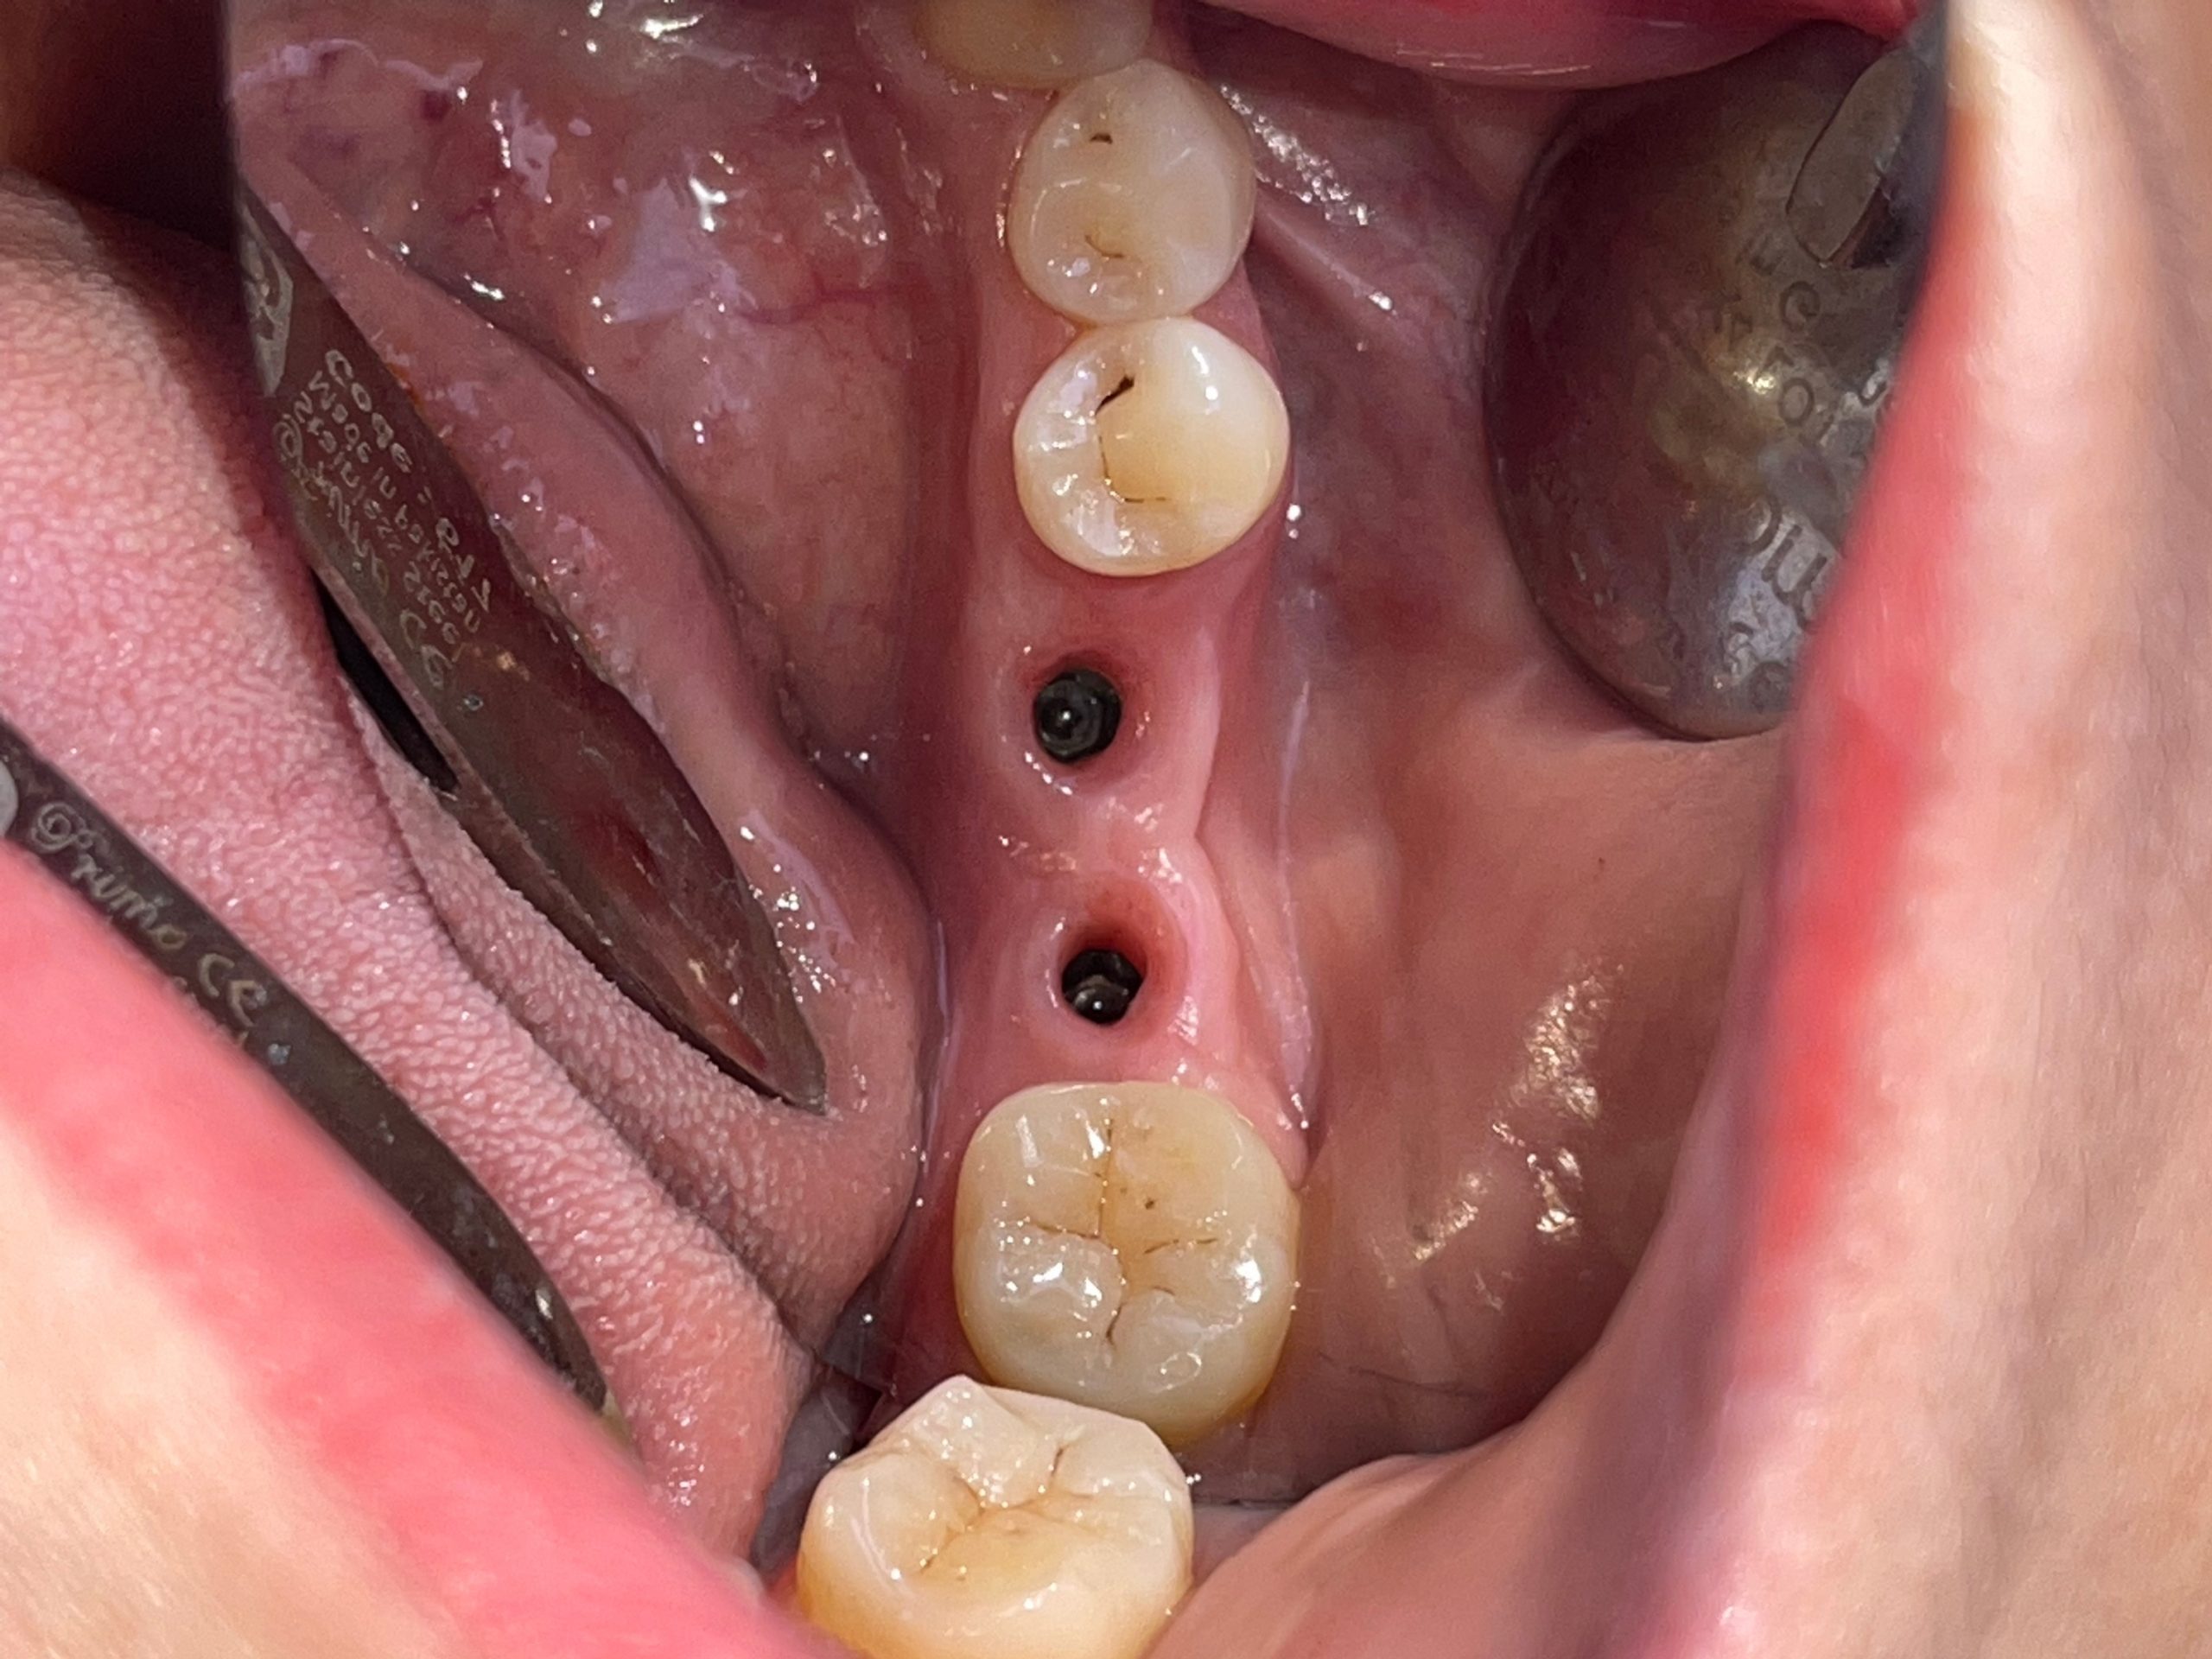

Bước 3: Phẫu thuật cấy ghép trụ Implant

Mọi ca cấy ghép Implant tại Nha khoa Bảo Mai đều được thực hiện trong phòng phẫu thuật riêng biệt, vô trùng tuyệt đối.

- Bác sĩ tiến hành gây tê để đảm bảo người bệnh cảm thấy thoải mái, không đau.

- Đặt trụ Implant vào xương hàm.

Nhờ kỹ thuật hiện đại, quá trình này diễn ra khá nhẹ nhàng, ít đau hơn nhiều so với tưởng tượng, thời gian thực hiện khoảng 20 – 30 phút/trụ.